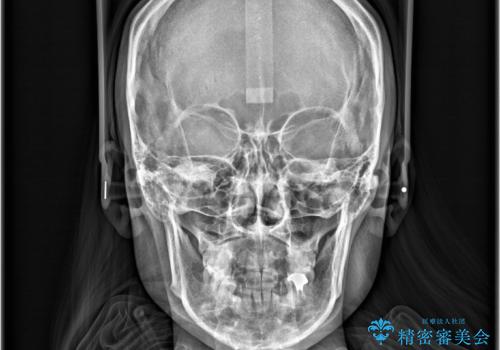

- 「歯のデコボコ、八重歯、口ボコが気になる」を主訴に来院された患者様です。

上下左右4番(4本)の歯を抜歯しワイヤー矯正で治療を行いました。

計4本の抜歯を行い、歯のデコボコと口元がすっきりし、大変ご満足していただけました。